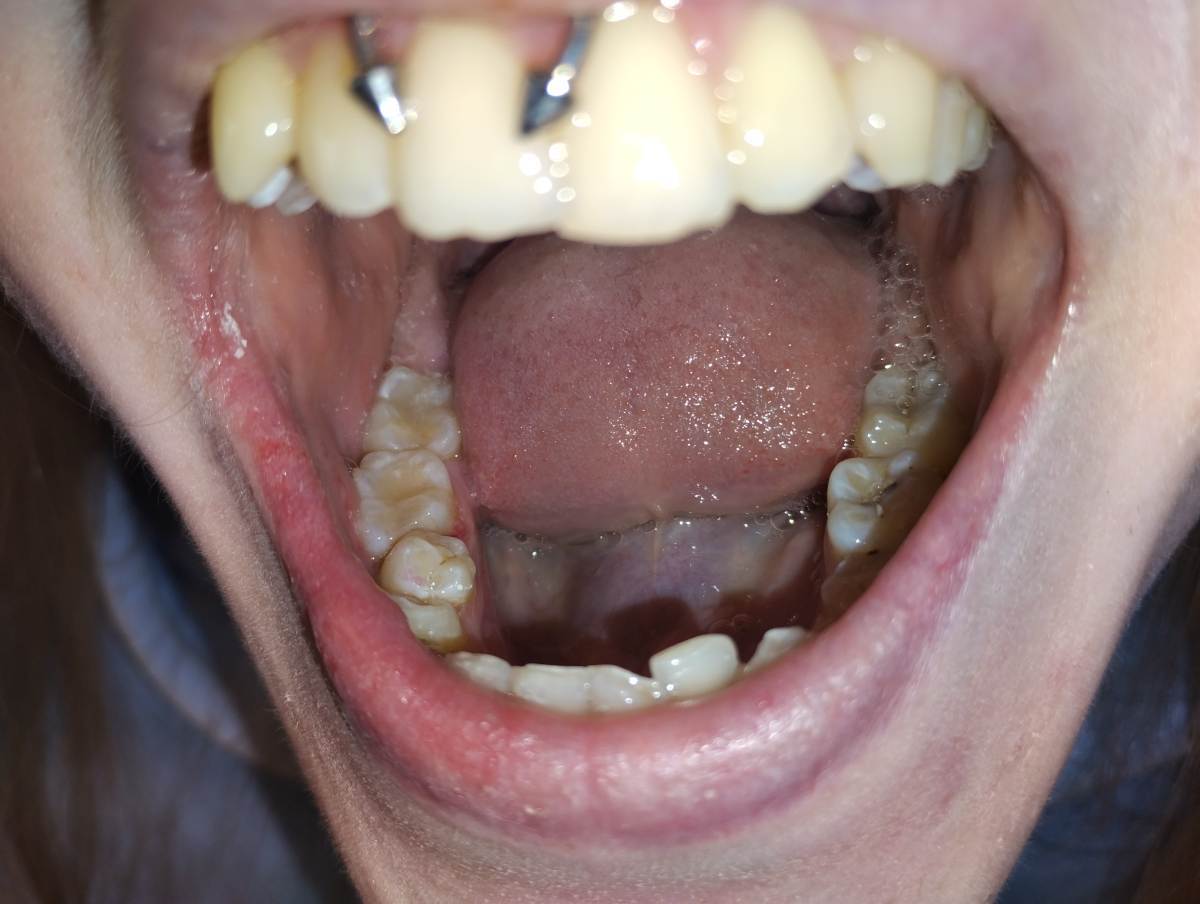

Александр1 Опубликовано 29 апреля Автор Поделиться Опубликовано 29 апреля (изменено) Извините, только такие(до и после) Изменено 29 апреля пользователем Александр1 Ссылка на комментарий

АнтонТЛТ Опубликовано 29 апреля Поделиться Опубликовано 29 апреля Отметьте, где болезненность Ссылка на комментарий

Александр1 Опубликовано 30 апреля Автор Поделиться Опубликовано 30 апреля В этой точке, пациент говорит в самом углу, боль ощущается при зондировании пломбы, сами ткани зуба безболезненны Ссылка на комментарий